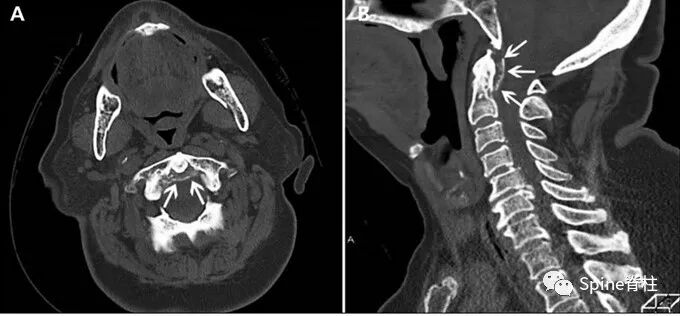

【病例2】2014年Kuriyama等发表在加拿大医学杂志(CMAJ)的病例。

一位84岁的男性患者,因“急性颈痛、僵硬伴发热”就诊。查体:颈椎向各个方向活动受限,无明显神经病变体征。实验室检查:血沉及C反应蛋白偏高。颈椎CT平扫提示齿状突横韧带钙化(箭头所示),从而诊断为齿状突加冠综合征。给予洛索洛芬治疗一周后,上述症状完全缓解,而且炎性指标恢复正常。

患者女,76岁。无明显诱因下出现颈部疼痛、僵硬伴发热 3 d 入院 ,颈部疼痛呈间歇性,颈痛视觉模拟评分(VAS)为7分,体温37.7~38.8℃,无四肢疼痛麻木,无行走不稳,二便正常。既往无痛风、类风湿关节炎病史。入院体检:颈椎旋转明显受限,颈部肌肉僵硬,未查及明显神经或脊髓损伤体征。实验室检查:白细胞11.2×109/L,红细胞沉降率35.4 mm/h,超敏C反应蛋白14.7 mg/L,类风湿因子及降钙素原正常。颈椎CT平扫示齿状突后侧寰椎横韧带弧形钙化(左图箭头)和竖直线样钙化(右图箭头)。依据患者病史、体征及辅助检查,齿状突加冠综合征可基本诊断。入院后给予氯诺昔康 8 mg静脉滴注每日2次,地塞米松起始量10 mg静脉滴注每日1次,3日后改为5mg/d。连续治疗5 d后,患者入院时症状明显缓解,复查白细胞、红细胞沉降率、超敏C反应蛋白均恢复正常。随访半年,未有颈痛伴发热症状出现。